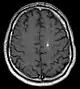

| Histology of a cavernous hemangioma | |

Diagnosis is generally made by magnetic resonance imaging (MRI), particularly using a specific imaging technique known as a gradient-echo sequence MRI, which can unmask small or punctate lesions that may otherwise remain undetected. These lesions are also more conspicuous on FLAIR imaging compared to standard T2 weighing. FLAIR imaging is different from gradient sequences. Rather, it is similar to T2 weighing but suppresses free-flowing fluid signal. Sometimes quiescent CCMs can be revealed as incidental findings during MRI exams ordered for other reasons. Many cavernous hemangiomas are detected "accidentally" during MRIs searching for other pathologies. These "incidentalomas" are generally asymptomatic. In the case of hemorrhage, however, a CT scan is more efficient at showing new blood than an MRI, and when brain hemorrhage is suspected, a CT scan may be ordered first, followed by an MRI to confirm the type of lesion that has bled.[19] Sometimes the lesion appearance imaged by MRI remains inconclusive. Consequently, neurosurgeons will order a cerebral angiogram or magnetic resonance angiogram. Since CCMs are low flow lesions (they are hooked into the venous side of the circulatory system), they will be angiographically occult (invisible). If a lesion is discernible via angiogram in the same location as in the MRI, then an arteriovenous malformation (AVM) becomes the primary concern.